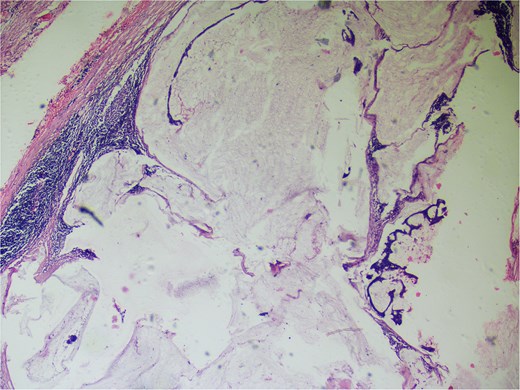

On gross examination, growth seen involving ileocecal junction extending upto caecum measuring 6.5 × 6.0 × 4.3 cm. Cut section showed solid creams white firm to friable areas with mucoid consistency at places. A nodular growth is identified in the attached mesentery measuring 3.5 × 2 × 2 cm. On cut section solid white areas are seen along with focal area showing mucoid consistency. The histopathological report concluded mucinous adenocarcinoma of caecum, pT3N1MX, with evidence of lymphovascular invasion. The tumor invaded through the muscular propria layer (Figs 4 and 5). Additionally, acute appendicitis was found.

Hemotoxylin and eosin ×100: Section shows atypical cells floating in lates of extra cellular mucin.